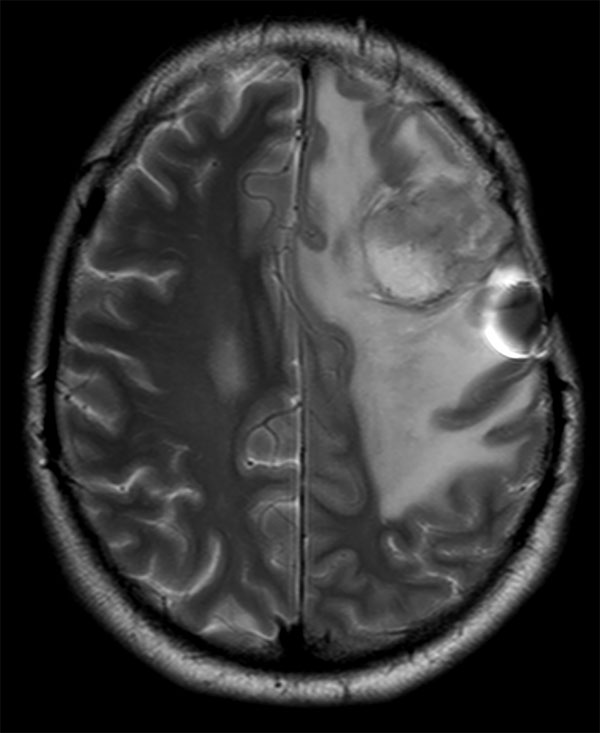

Axial T2w TSE